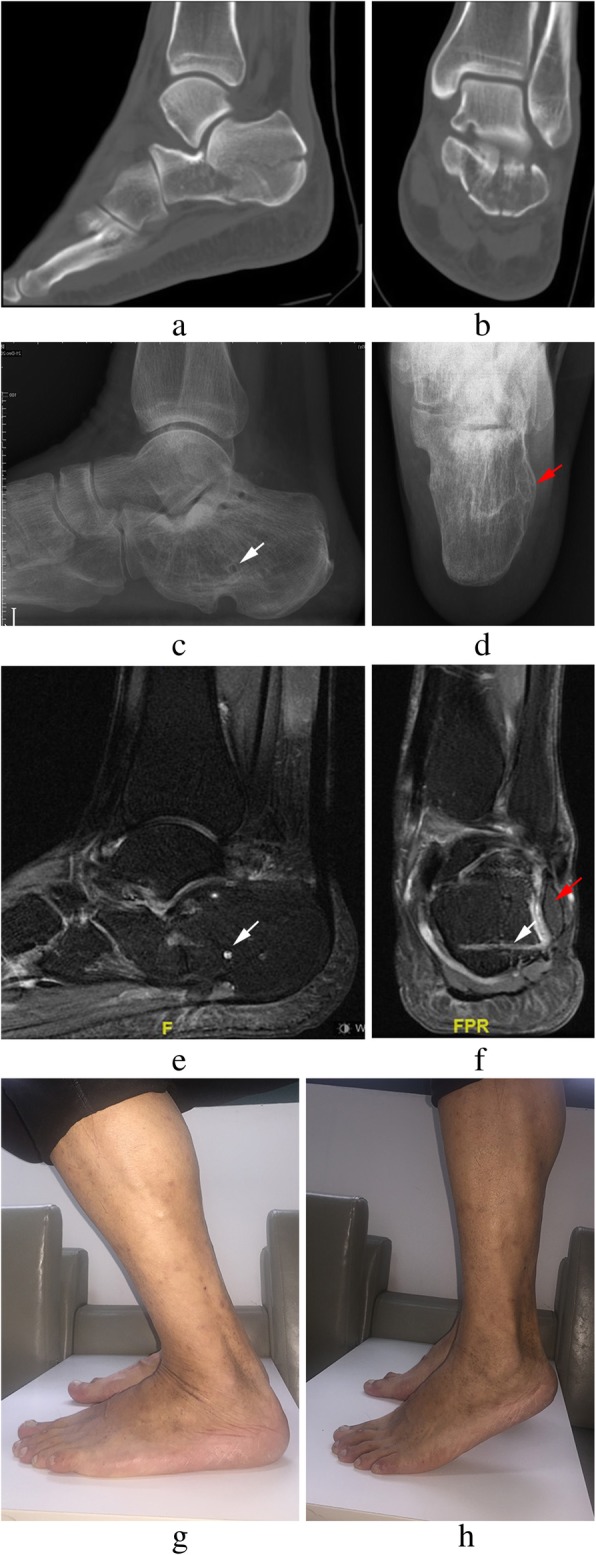

Fig. 3.

Radiographs of a 43-year-old male patient admitted for left calcaneal fractures of Sander’s type III (a, b). Lateral (c) and axial (d) views at 36 months post-surgery showing bony union of the fracture and the lateral wall (red arrow); several screw holes remain (white arrow). Sagittal and coronal MR images (e, f) showing partial absorption of biodegradable implants. The extension range of motion (g) and the flexion range of motion (h) at the final follow-up are displayed